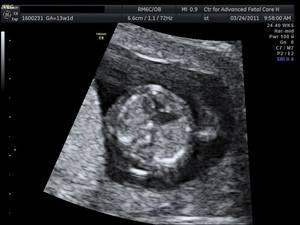

Photo courtesy Dr. Christopher Harman

Figure 3. 3-D blocks analyzed by tomographic section in a systematic approach, yield complete catalogue of anatomic cardiac landmarks in over 80% of fetuses at 12 weeks.

Indeed, significant improvements in the overall computing capability of modern ultrasound equipment, in three-dimensional color ultrasonography, and in ultrasound image resolution – as well as specific new technologic developments such as tomographic imaging and spatiotemporal image correlation – have opened the door to first-trimester cardiac screening.

In the majority of patients, up to 12 parameters of fetal cardiac structure can be visualized. Each of the three segments of the exam takes only a few seconds to perform, so the actual collection of information is rapid. The technologic advances have also made the acquisition of images easier and less operator dependent. Moreover, the analysis is then performed offline, so the mother can go home afterward. Offline analysis of images also means that the ultrasound scan itself can be performed by trained sonographers at a distance from a cardiac center, with the information transmitted to the center for expert analysis.

It wasn’t long ago that second-trimester fetal echocardiography was the gold standard for any prenatal evaluation of fetal cardiac structure and function. Now, with an early and integrated screening approach that utilizes first-trimester fetal cardiac examination, we can in fact diagnose many of the most severe heart defects as early as 12 weeks of gestation. At this stage, the fetal heart is as small as the tip of the little finger.